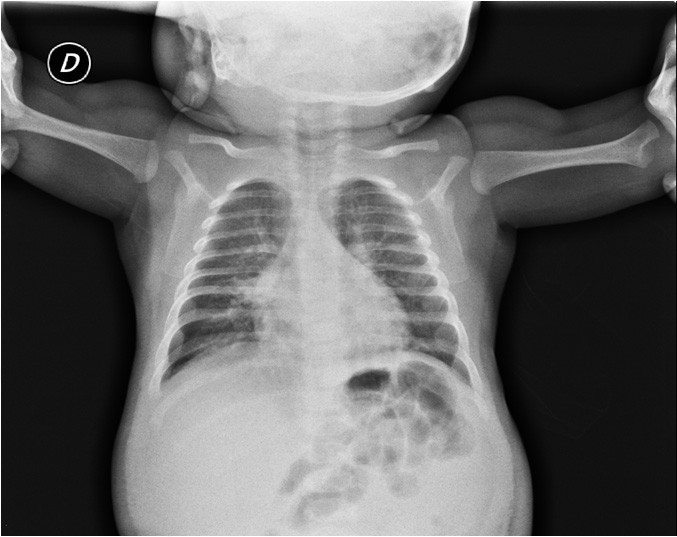

Severe Kawasaki disease in a 3monthold patient a case report BMC Case Report Kawasaki Disease Kawasaki disease (kd) is the leading cause of acquired heart disease in children in developed countries. Kawasaki disease is multisystem vasculitis affecting young children and infants. Kawasaki disease (kd) is the leading cause of acquired heart disease in children in developed countries. Kawasaki disease (kd) is a systemic vasculitis and the leading cause of acquired heart disease in the developed. Case Report Kawasaki Disease.